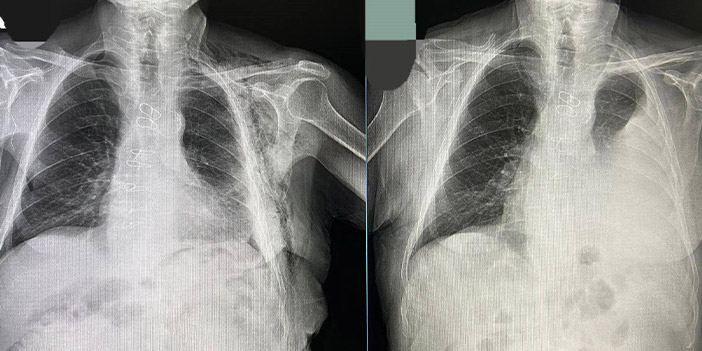

Bayburt Devlet Hastanesinde bir hastaya kapalı yöntemle akciğer ameliyatı yapıldı. 80 yaşındaki hasta, geçirdiği operasyonun ardından sağlığına kavuştu.

Bypass ameliyatı sonrası Göğüs Cerrahisi Polikliniğine kontrole giden hastanın göğüs boşluğunda sıvı biriktiği tespit edildi.

Tüp torakostomiye dirençli efüzyon nedeniyle değerlendirmeye alınan hastaya Göğüs Cerrahisi Uzmanı Op. Dr. Halil Kolcu tarafından kapalı yöntemle akciğeri serbestleme ameliyatı yapıldı.

Başarılı geçen operasyonla hastanın akciğerinin yeniden genişlemesi sağlanırken, sıvı birikiminin önüne geçildi. Hastanın ameliyat sonrası sürecinin sorunsuz ilerlediği ve altıncı günde taburcu edildiği öğrenildi.